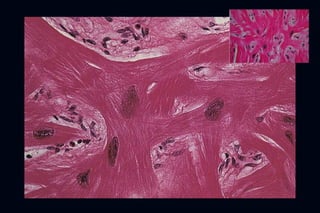

–   Los hallazgos histológicos fundamentales son la

hipertrofia desorganizada y fibrosis (disarray)

–   También existe afectación de las arterias coronarias

con hiperplasia de la intima, fibrosis y reducción de

su lumen (SICAD)

Small Intramural coronary arteriole dysplasia (SICAD)

Kwon et al. JACC 2009

FISIOPATOLOGIA – Enfermedad del sarcómero – Los hallazgos histológicos fundamentales son la hipertrofia desorganizada y fibrosis (disarray) – También existe afectación de las arterias coronarias con hiperplasia de la intima, fibrosis y reducción de su lumen (SICAD)

Small Intramural coronaryarteriole dysplasia (SICAD) Kwon et al. JACC 2009